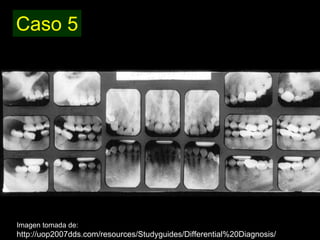

Dentinogénesis imperfecta es una condición genética que causa un disturbio en la formación de la dentina. Existen tres tipos principales. El tipo I se asocia con osteogénesis imperfecta. El tipo II solo afecta la dentina y causa dientes amarillos o grises con atrición. El tipo III es raro y se encuentra en un área aislada de Maryland, con exposiciones pulpares frecuentes. Todos los tipos muestran características radiográficas como obliteración de cámaras y conductos,